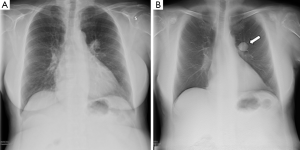

Compared to standard radiography, DCT has several advantages like improved lesion detection due to a reduction in anatomical noise or composite artefact, better depth localisation and contrast resolution. Recent reports have shown that the use of tomosynthesis, as an alternative of CR, leads to considerable improvement in diagnostic information without an increase in radiation dose (Figure 2).